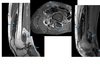

Chondrosarcoma

May be cecondary to

- Osteochondromas

- enchondromas

Chondrosarcomas occur in the pelvis, femur, humerus.

Skull base, TMJ

DDX

-Most well differentiated, low grade = ‘low grade chondroid lesion’ , cant differentate from enchondroma

-Bone infarct

MRI

Lobular growth

High 2 signal/STIR, low T1

ring and arcs/chondroid matrix islands on CT

Soft tissue extension

**endosteal scalloping. **

if no mineralized matrix/rings and arcs = aggressive/high grade

How to tell chondrosarcoma from enchondroma ?

* Pathological fracture occurring with minimal trauma

* Multilayered or spiculate periosteal reaction

* Permeative or moth-eaten osteolysis

* Cortical destruction

* A soft tissue mass

Endosteal scalloping more than 2/3 cortex